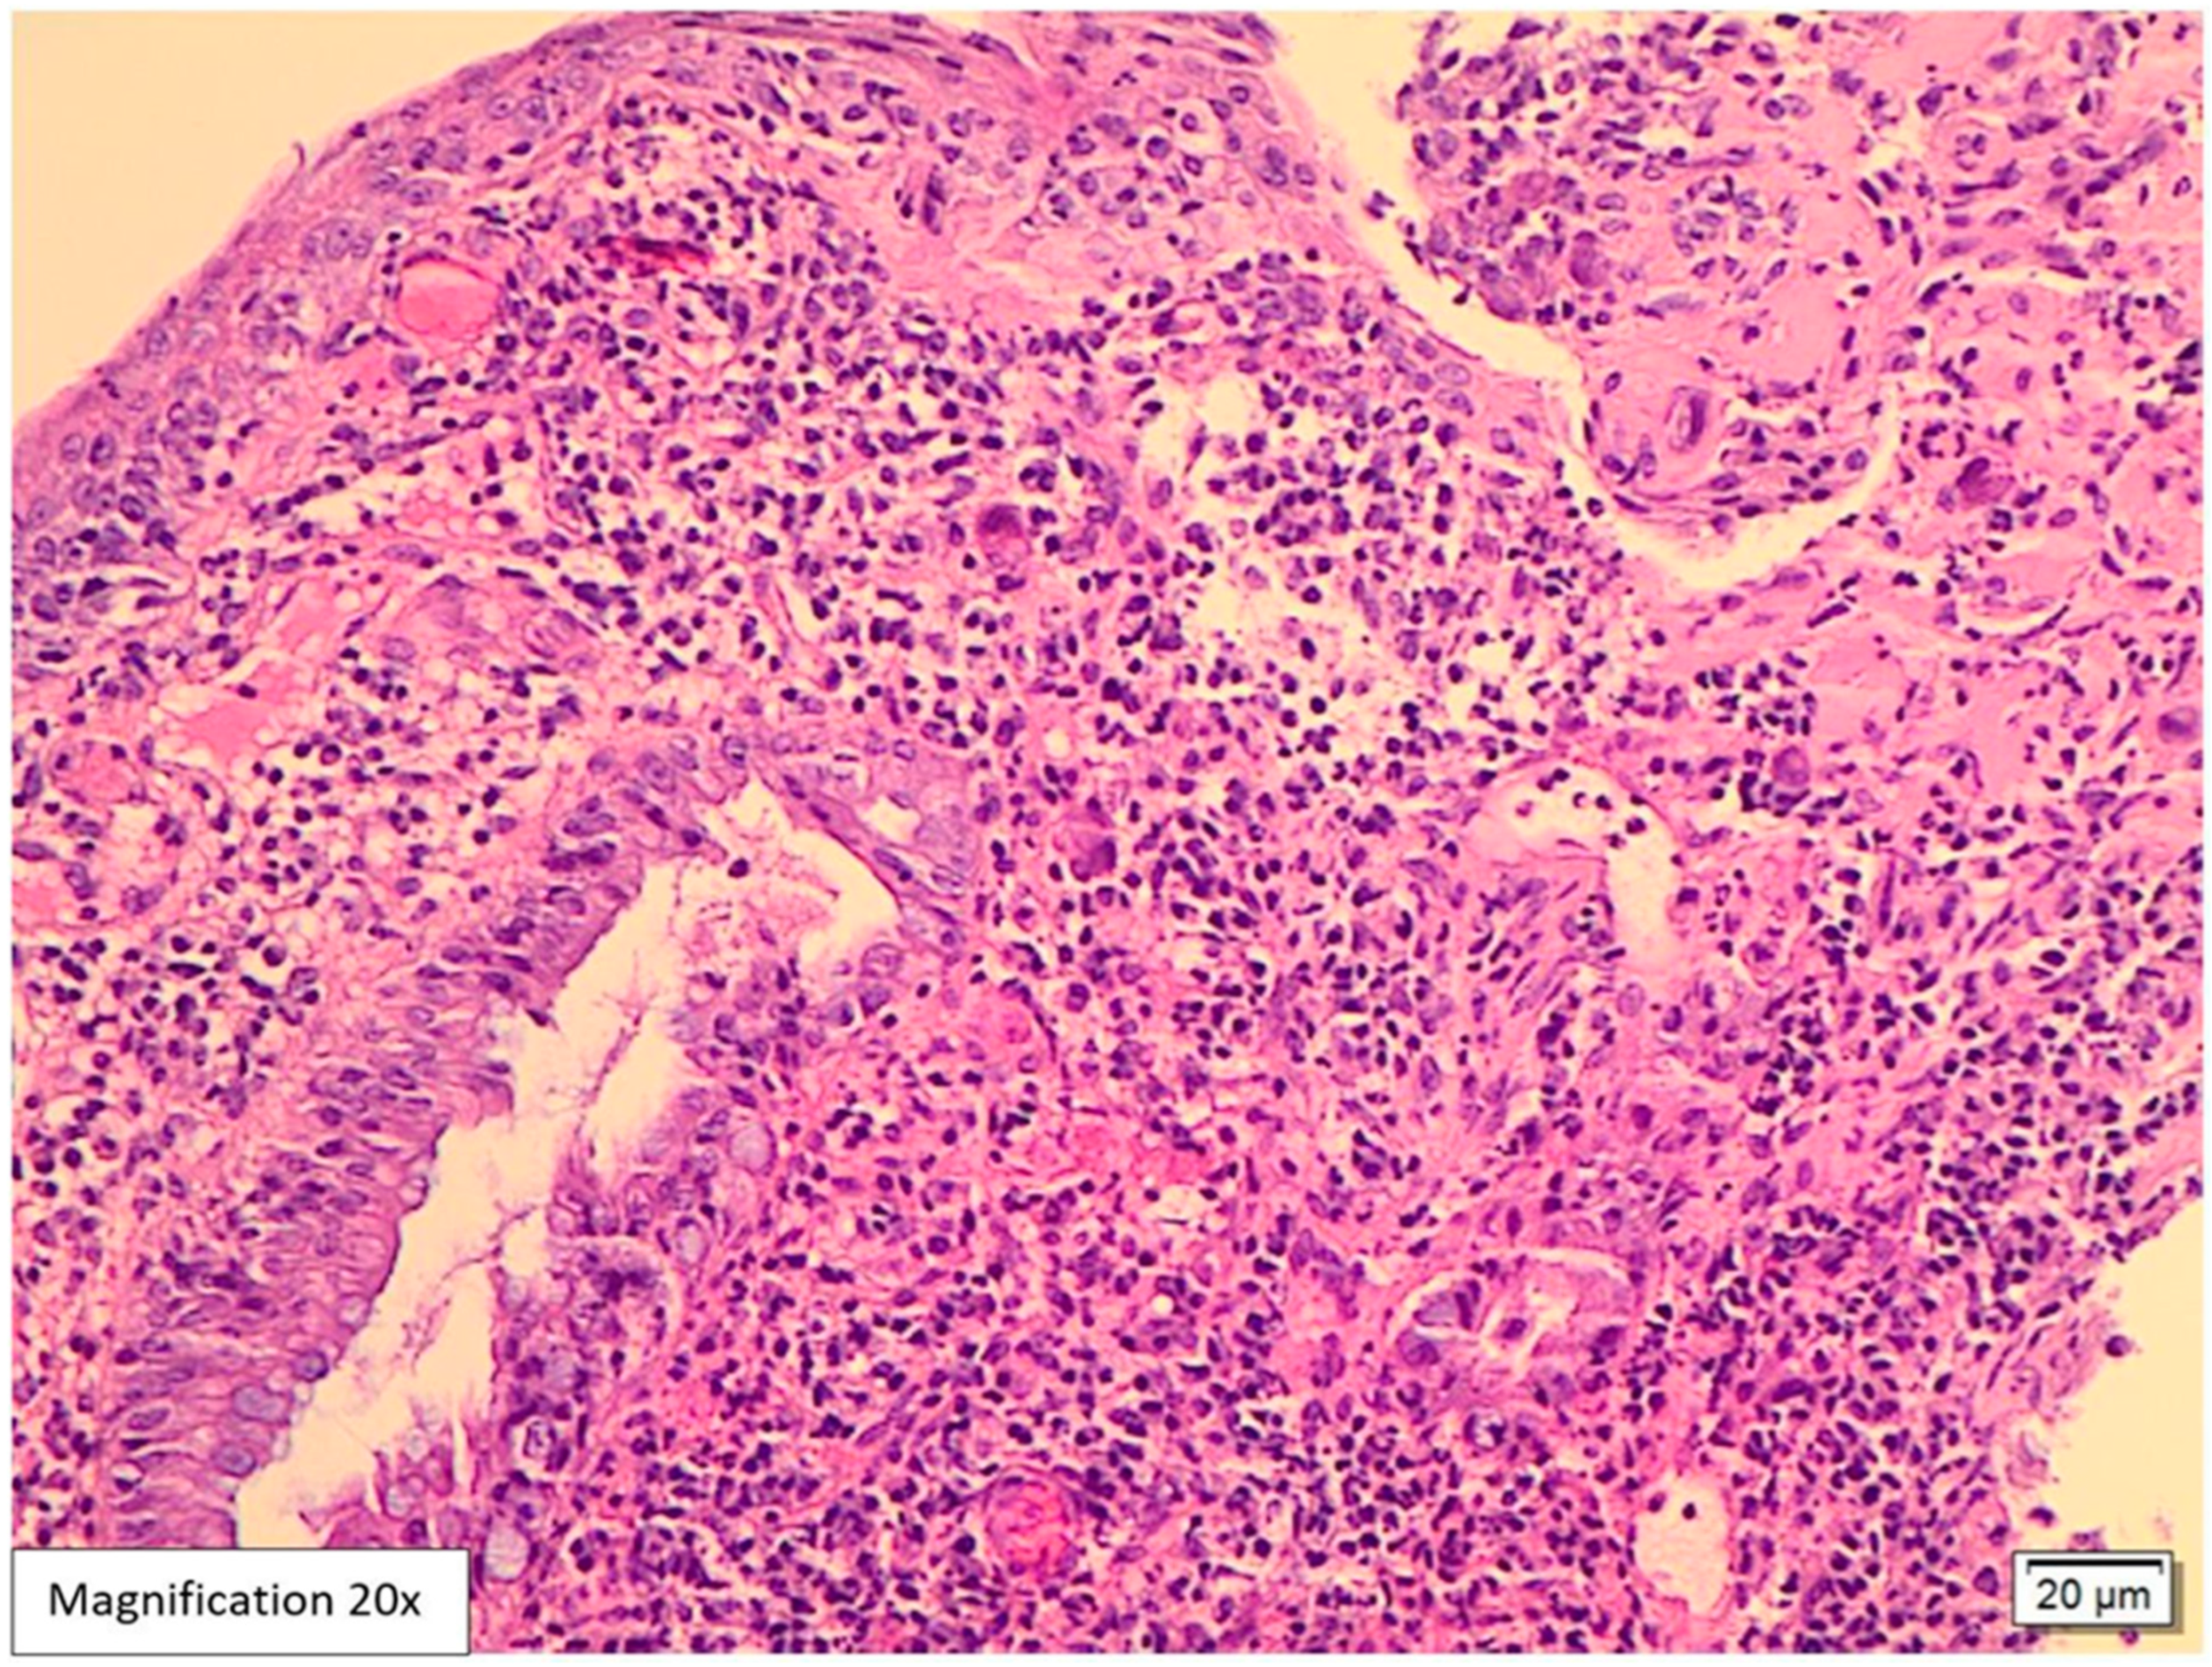

Case Presentation